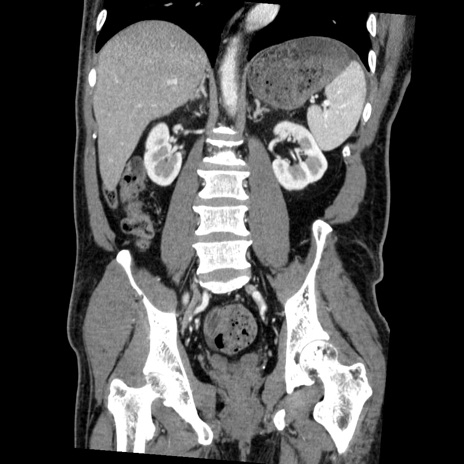

症例22(冠状断像)

【症例】50歳代男性

【主訴】腹痛

【現病歴】AVMからの被殻出血のため回復期リハ病棟入院中。 本日午後3時頃急に下腹部痛が出現した。

【既往歴】AVM、被殻出血、虫垂炎、高血圧

【身体所見】意識晴明、左半身不全麻痺、会話の理解は良好、36.5°C、腹部:膨隆、全体に板状硬、下腹部正中に圧痛点あり、反跳痛-、筋性防御不明、右下腹部にope scar

【データ】WBC 9400、CRP 0.06